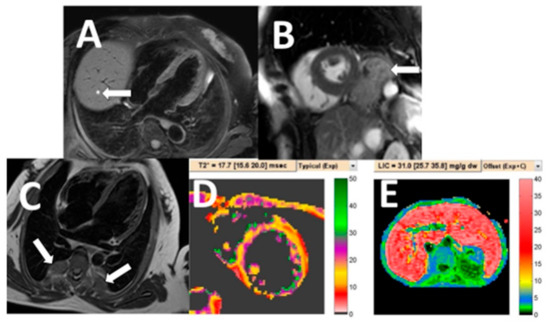

| Extramedullary hematopoiesis | 5 (5.4) |